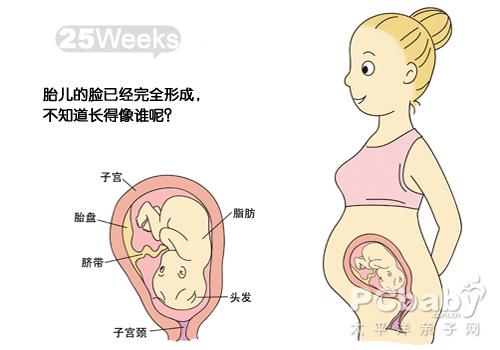

怀孕5个月怀孕5个月也就是孕20周左右,此时大部分准妈妈都能明显感觉到宝宝的胎动了,通过B超,我们可以看到胎宝宝已经发育的比较大了,其“紧握”着的小手也清晰可见,真是可爱极了。到这个月份,准妈妈的肚子应该也已经显怀了,此时别忘了适量运动哦。